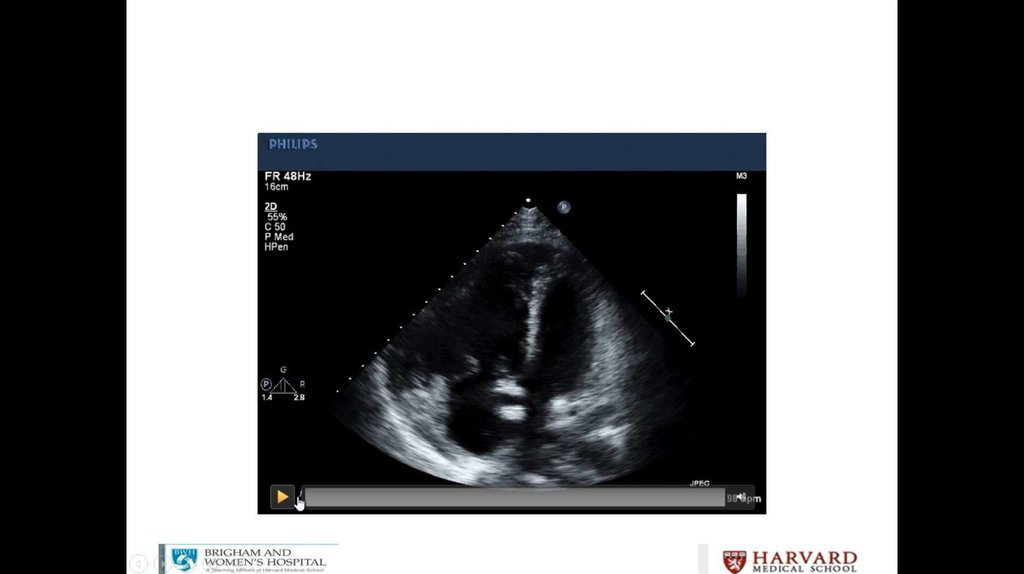

Litrasound in the ICU: What Every Intensivist Should Know